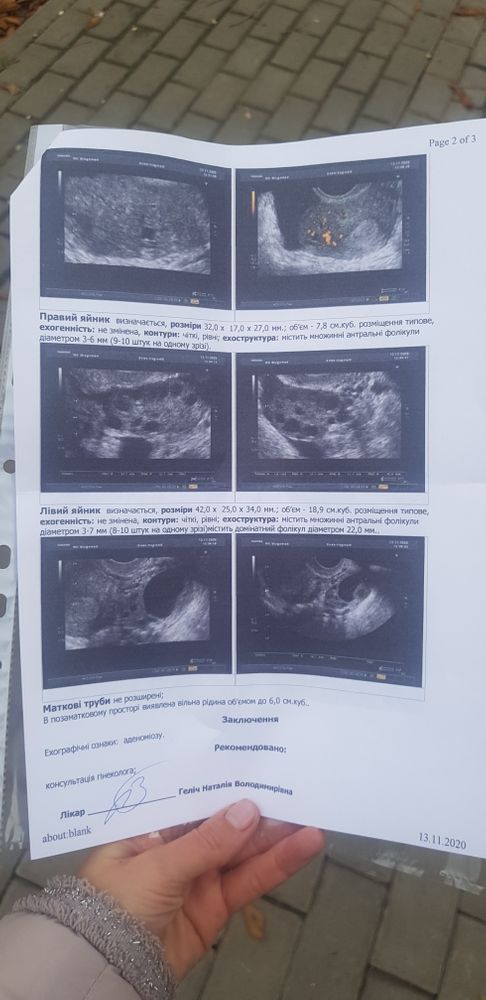

Тяжело судить. Надо непосредственно на узи смотреть. Если это гормональный сбой после выкидыша и овуляция только сейчас (судя по доминантному фолликулу) , то через недели 2 только месячные будут.

ТыКатя, у меня типа эндометрий 13мм, она сказала что М начинаются при 15 мм+- И гормоны сдавала почти сразу после В, как всё вышло то были впорядке, ну только прогестерон низковат

ТыКатя, только там всё на укр языке